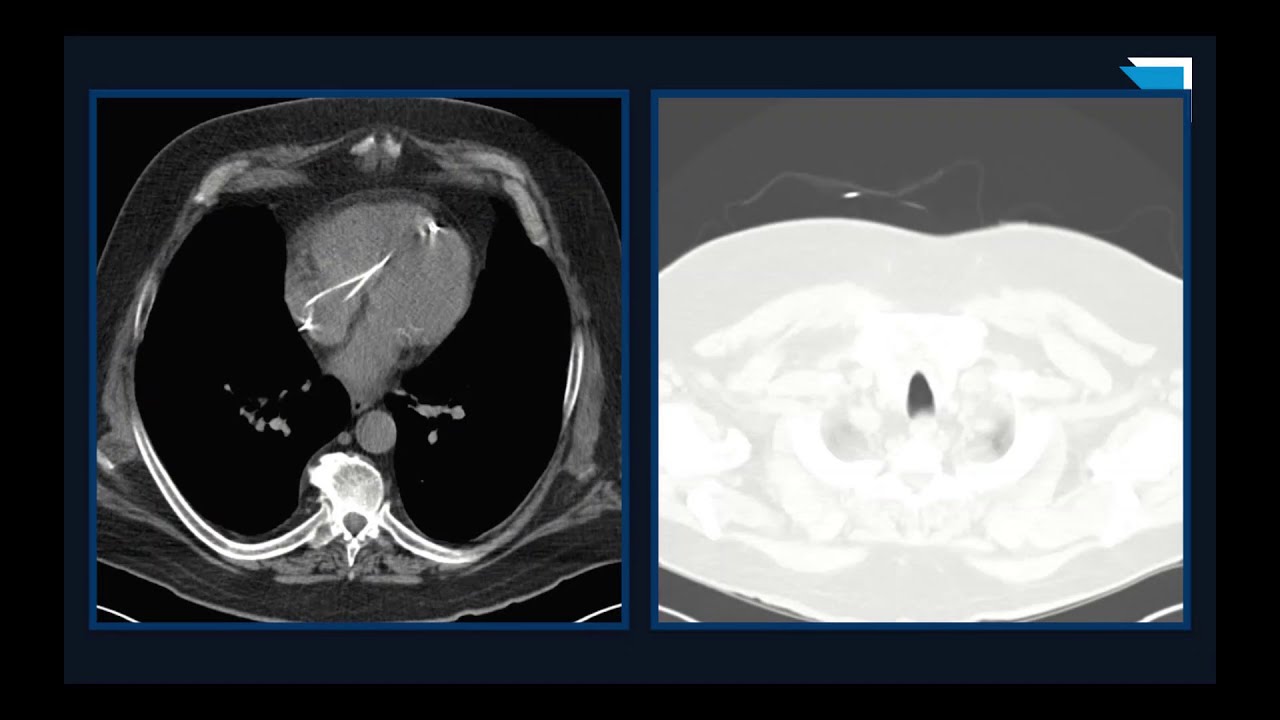

Great Calls! | 15 Minute Radiology CME

1. Learn the importance of maintaining a standard search pattern when reviewing images.

2. Learn how secondary signs can be used to identify fractures.